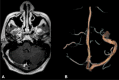

A MR with gadolinium. Right transverse and sigmoid sinuses with partial enhancement due to subacute thrombosis. B MR angiography with significant decrease of the venous flow in the right transverse and sigmoid sinuses due to partially recanalized thrombosis